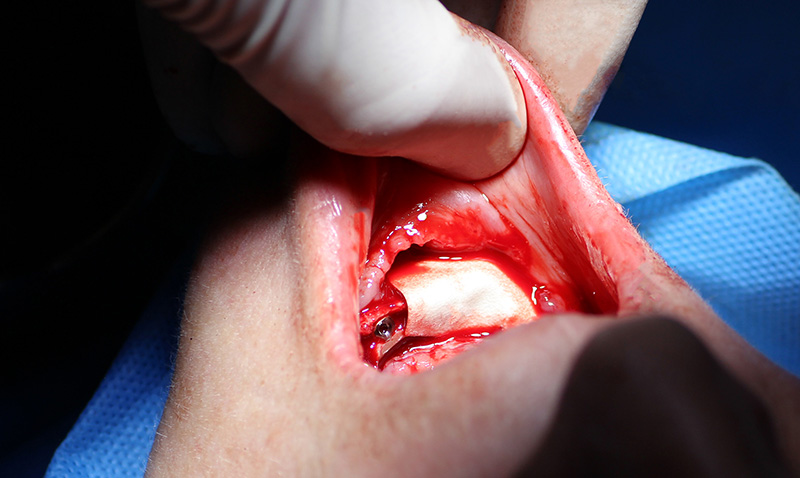

Мастер-Класс «Одномоментная Имплантация С Аугментацией Кости», с использованием имплантатов Alfa Gate

25-ого октября в учебном центре Стом-Лайн был проведен мастер-класс на тему «Одномоментная имплантация с аугментацией (наращиванием) кости, с использованием имплантатов Alfa Gate Dental Implants». Мастер-класс провел главный врач-стоматолог клиники «Нюанс» в Москве Мхитар Казарян.

Мастер-класс начался с обсуждения предстоящей операции и исследования компьютерной томографии, после чего участники смогли присутствовать на операции или следить за ней из учебного центра.